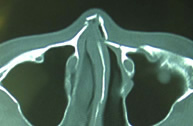

鼻骨の骨折は顔面骨の骨折の中で最も多い骨折です。受傷してから2~3週間以内であれば皮膚に傷つけずに治療することが可能です。原則的には、入院して全身麻酔による治療を行います。当科では、骨折の整復の状況(治り具合)を手術中に超音波診断装置を用いて評価することで、正確な治療を行っています。整復後は、鼻腔内にガーゼを詰めて、外側はプラスチック樹脂製のガードで固定を行います。受傷から1ヶ月以上経過した陳旧性では骨を切って整復する必要があります。その場合も鼻腔内の切開から行い表面には傷をつけずに行いますが、骨移植などを要することもあります。

| 鼻骨骨折CT像(整復前) | 鼻骨骨折CT像(整復後) |